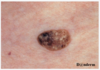

52- årig kvinde der gennem 5 år har haft en gradvist voksende, lysbrun tumor i venstre side af panden (foto). I samme periode er der tilkommet flere lignende elementer på truncus ledsaget af let kløe. Hun har aldrig været ivrig soldyrker.

- keratosis seborrhoica

Note: Alle svarmulighederne er mulige diagnoser. Den mest sandsynlige diagnose er keratosis seborrhoica (gammelmandsvorter)

De forekommer ofte i ansigt og øvre del af kroppen. De kan både være flade, men også eleverede som på billedet. De er pigmentede ligesom på billedet. Det har ikke rigtig symptomer udover kløe.

- Forkert - Umiddelbart vil man sagtens kunne tænke det da der er flere farver i samt nytilkommet, men den er symmetrisk og jar en jævn kant. Diameter ukendt. I takt med at hun har fået flere af dem på trunkus er det ikke sandsynligt, at der er tale om malignt melanom.

- Forkert - Hun har aldrig været ivrig soldyrker. I takt med at hun har fået flere af dem på trunkus er det ikke sandsynligt, at der er tale om cancer.

- Korrekt - jf. ovenstående note. Kan fryses eller skæres af (kryoterapi eller currettage) hvis kløen bliver for træls.

- Forkert - det kunne sagtens bare være et helt normalt modermærke. Dog er det ikke et “pænt” et af slagsen og anamnesen med flere tilkomne + udseende + kløen passere bedre på gammelmadsvorter (keratosis seborrhoica)